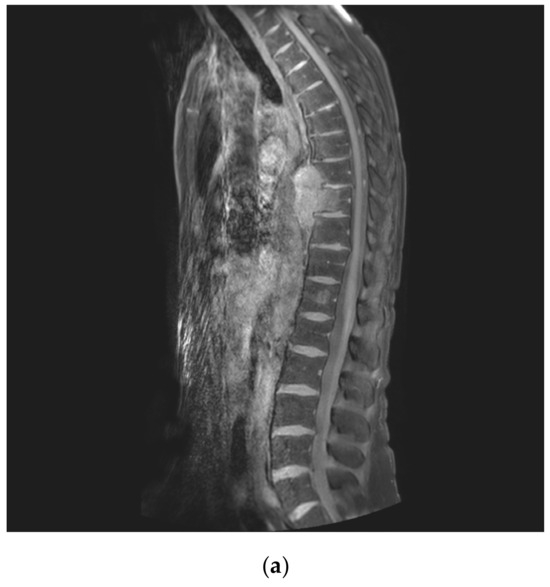

2.5. Reconstruction

2.7. Post-Operative Period and Follow Up